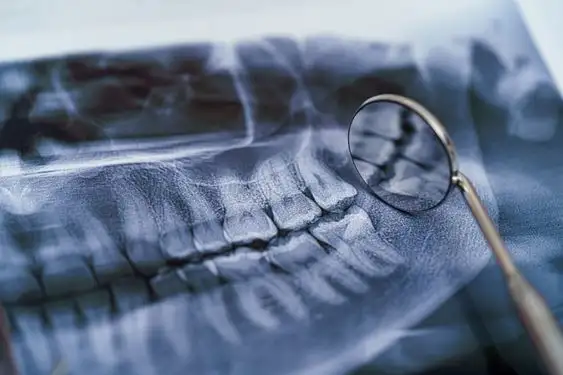

Детальний Огляд: Панорамний знімок зубів у Броварах